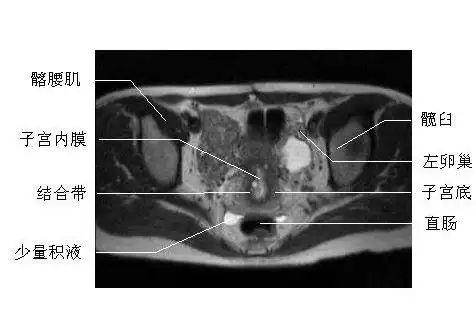

必须收藏!全网最全最详细女性盆腔mri解剖逐帧播放!

女性盆腔横断面mri图片

医学笔记|锋哥教你读盆腔核磁共振(3):经女性耻骨联合下份的横断层